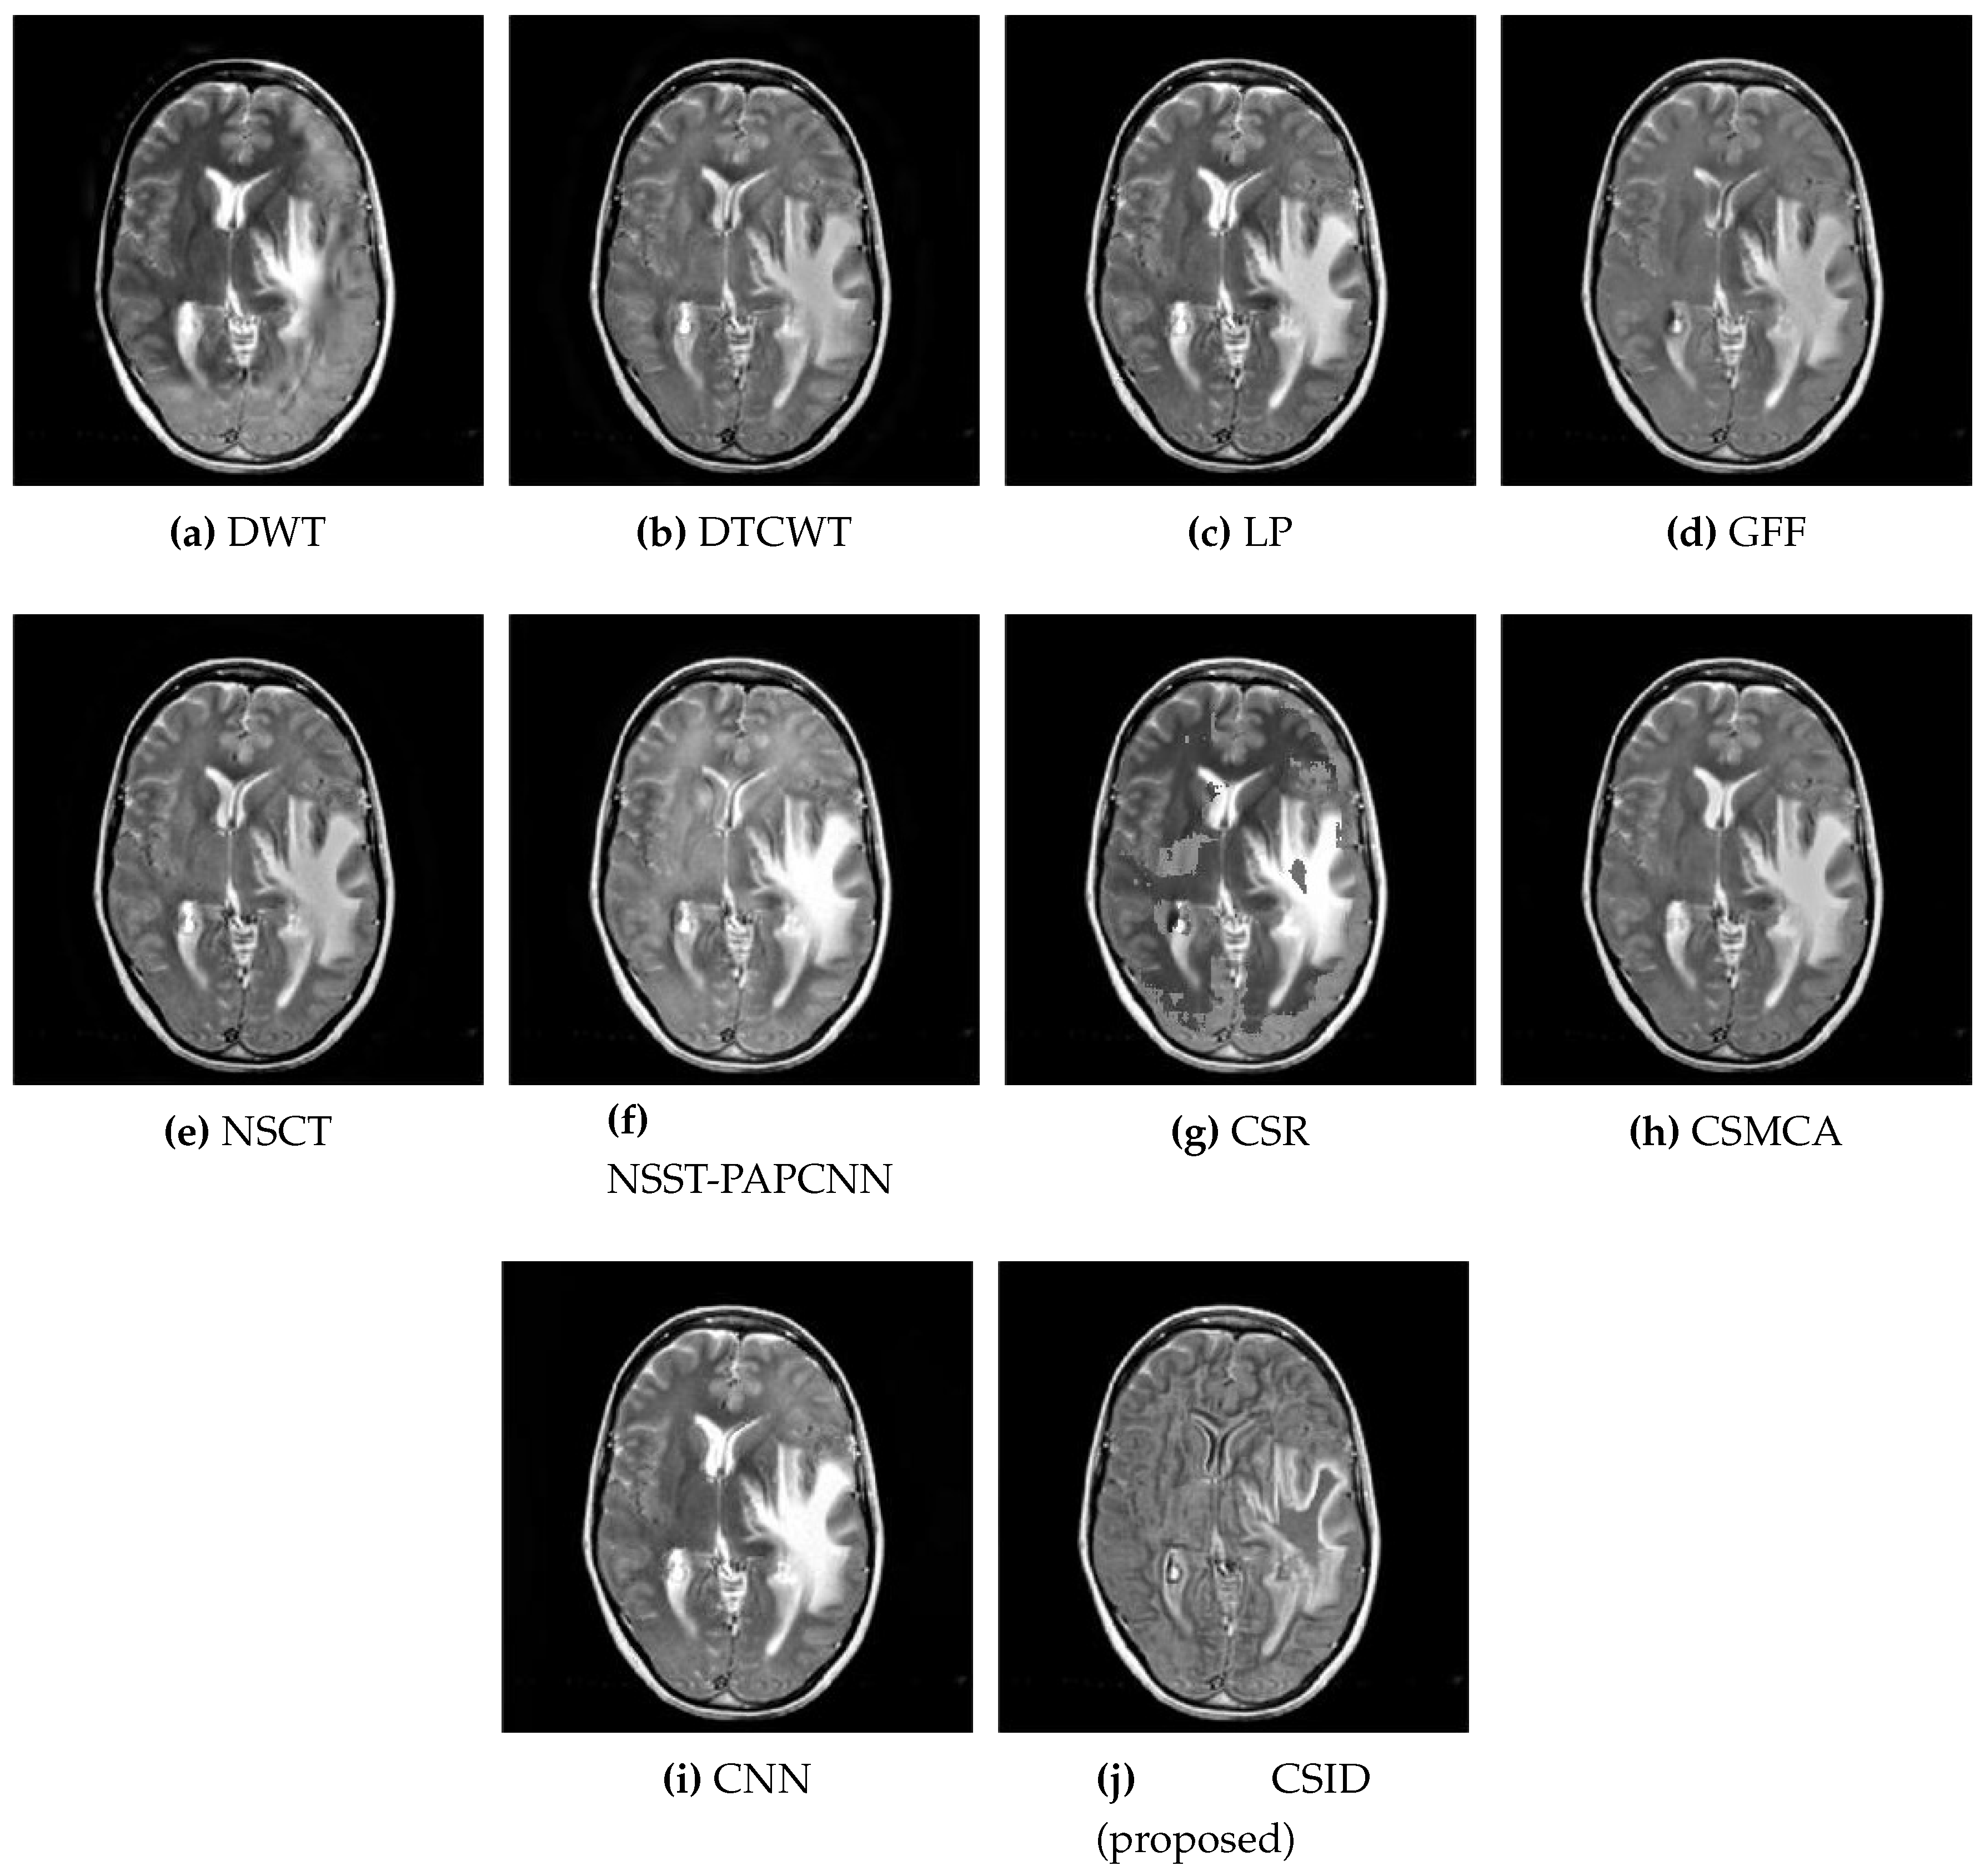

5.2.1. Qualitative Analysis of the Given Set of Algorithms for Multimodal Fusion